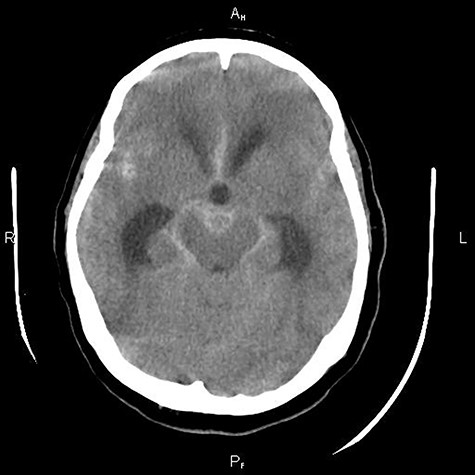

A 52-year-old patient was admitted to our hospital with a subarachnoid hemorrhage Hunt and Hess Grade 4 (Fig. 1). The digital subtraction angiography (DSA) revealed a complex basilar tip aneurysm (Fig. 2A). At the time of patient’s presentation in our clinic, there was no endovascular therapy option in our institution as our hospital lacked a neurointerventional infrastructure. As the optimal timing of surgically treating high-grade aneurysmal subarachnoidal hemorrhage is still controversial and our patient presented with hydrocephalus and a Hunt and Hess Grade 4 subarachnoidal hemorrhage, we first decided to treat the hydrocephalus with placement of an external ventricular drainage. The anatomical location of the aneurysm in the narrow space of interpeduncular fossa filled with blood clots and the severe brain edema were additional factors to the poor initial clinical presentation of the patient that made us decide for a delayed surgical treatment. Under intensive care therapy and treatment of the hydrocephalus with the external ventricular drainage, the clinical situation of the patient improved to Hunt and Hess Grade 3 preoperatively. We decided to clip the aneurysm under hypothermia and temporarycardiac arrest as the wide neck of the aneurysm, its large size and the narrow surgical space could not ensure the safe preparation of the aneurysm neck and the surrounding vessels and would also require a prolonged temporary clip application with increased ischemia risk if a technique with temporarily deflating the aneurysmal sac and allowing comfortable surgical maneuvres was not used. We conducted a thorough preoperative cardiological evaluation that revealed no contraindication for application of extracorporeal circulation using the heart–lung-machine. The operation took place 14 days after the rupture of the aneurysm. The surgical approach was done via a right-sided pterional craniotomy combined with orbitozygomatic osteotomy. Then, the sylvian fissure was opened; subsequently, the Liliequist membrane was opened through the optico-carotid cistern revealing the aneurysm. Following, a sternotomy and opening of the pericardium was performed by our cardiac surgeons. After intravenous administration of 35 000 IU heparin, an aortic and venous cannula was placed. The patient then was put on extracorporeal circulation with the use of heart–lung-machine and was cooled gradually down to 18°C (Fig. 3). At this point, a circulatory arrest was caused by stopping the heart–lung-machine. Simultaneously, the head of the operating table was elevated to promote emptying the blood from the aneurysm sac. Thanks to these manipulations, an efficient and comfortable microsurgical preparation of the aneurysm and its neck from the surrounding small perforating arteries and the proximal branches of the basilar artery was achieved. Hereafter, a clip was placed uneventfully occluding the aneurysm. We gradually rewarmed the patient up to 36.5°C in the following 15 minutes. After administration of protamine sulfate to antagonize the previously administered heparin, the surgery proceeded with the closure of the craniotomy and the thoracotomy. No postoperative complications were recorded and the patient was able to exit the intensive care unit in 8 weeks. A postoperative DSA confirmed the complete occlusion of the aneurysm (Fig. 2B). The patient was transferred 18 weeks after the operation with no focal neurological deficits at the referring hospital.